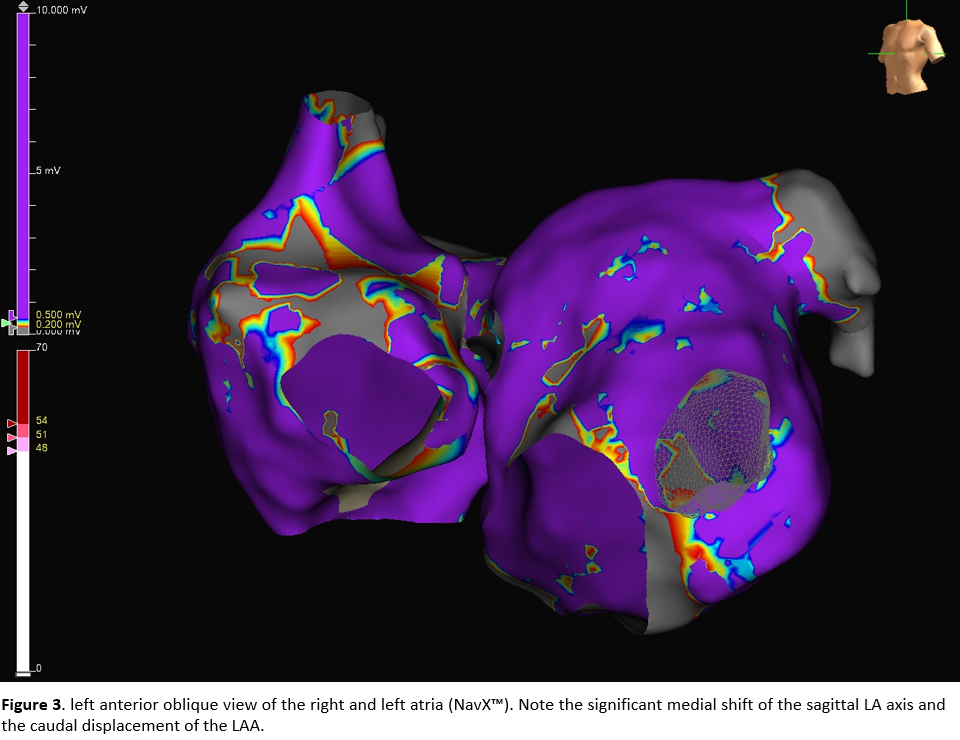

Electroanatomic mapping was performed with the EnSite™ NavX™. A significant medial shift of the left atrial sagittal axis was observed, along with a leftward and caudal displacement of the left atrial appendage. In nearly most of the left atrium, endocardial bipolar voltage was <1.5 mV, with only scattered low-voltage areas (LVA) <0.5 mV. The lateral pulmonary veins demonstrated preserved antral conduction, likely reflecting a previously deep balloon position. On the septal aspect, conduction into the RCPV was fully preserved.